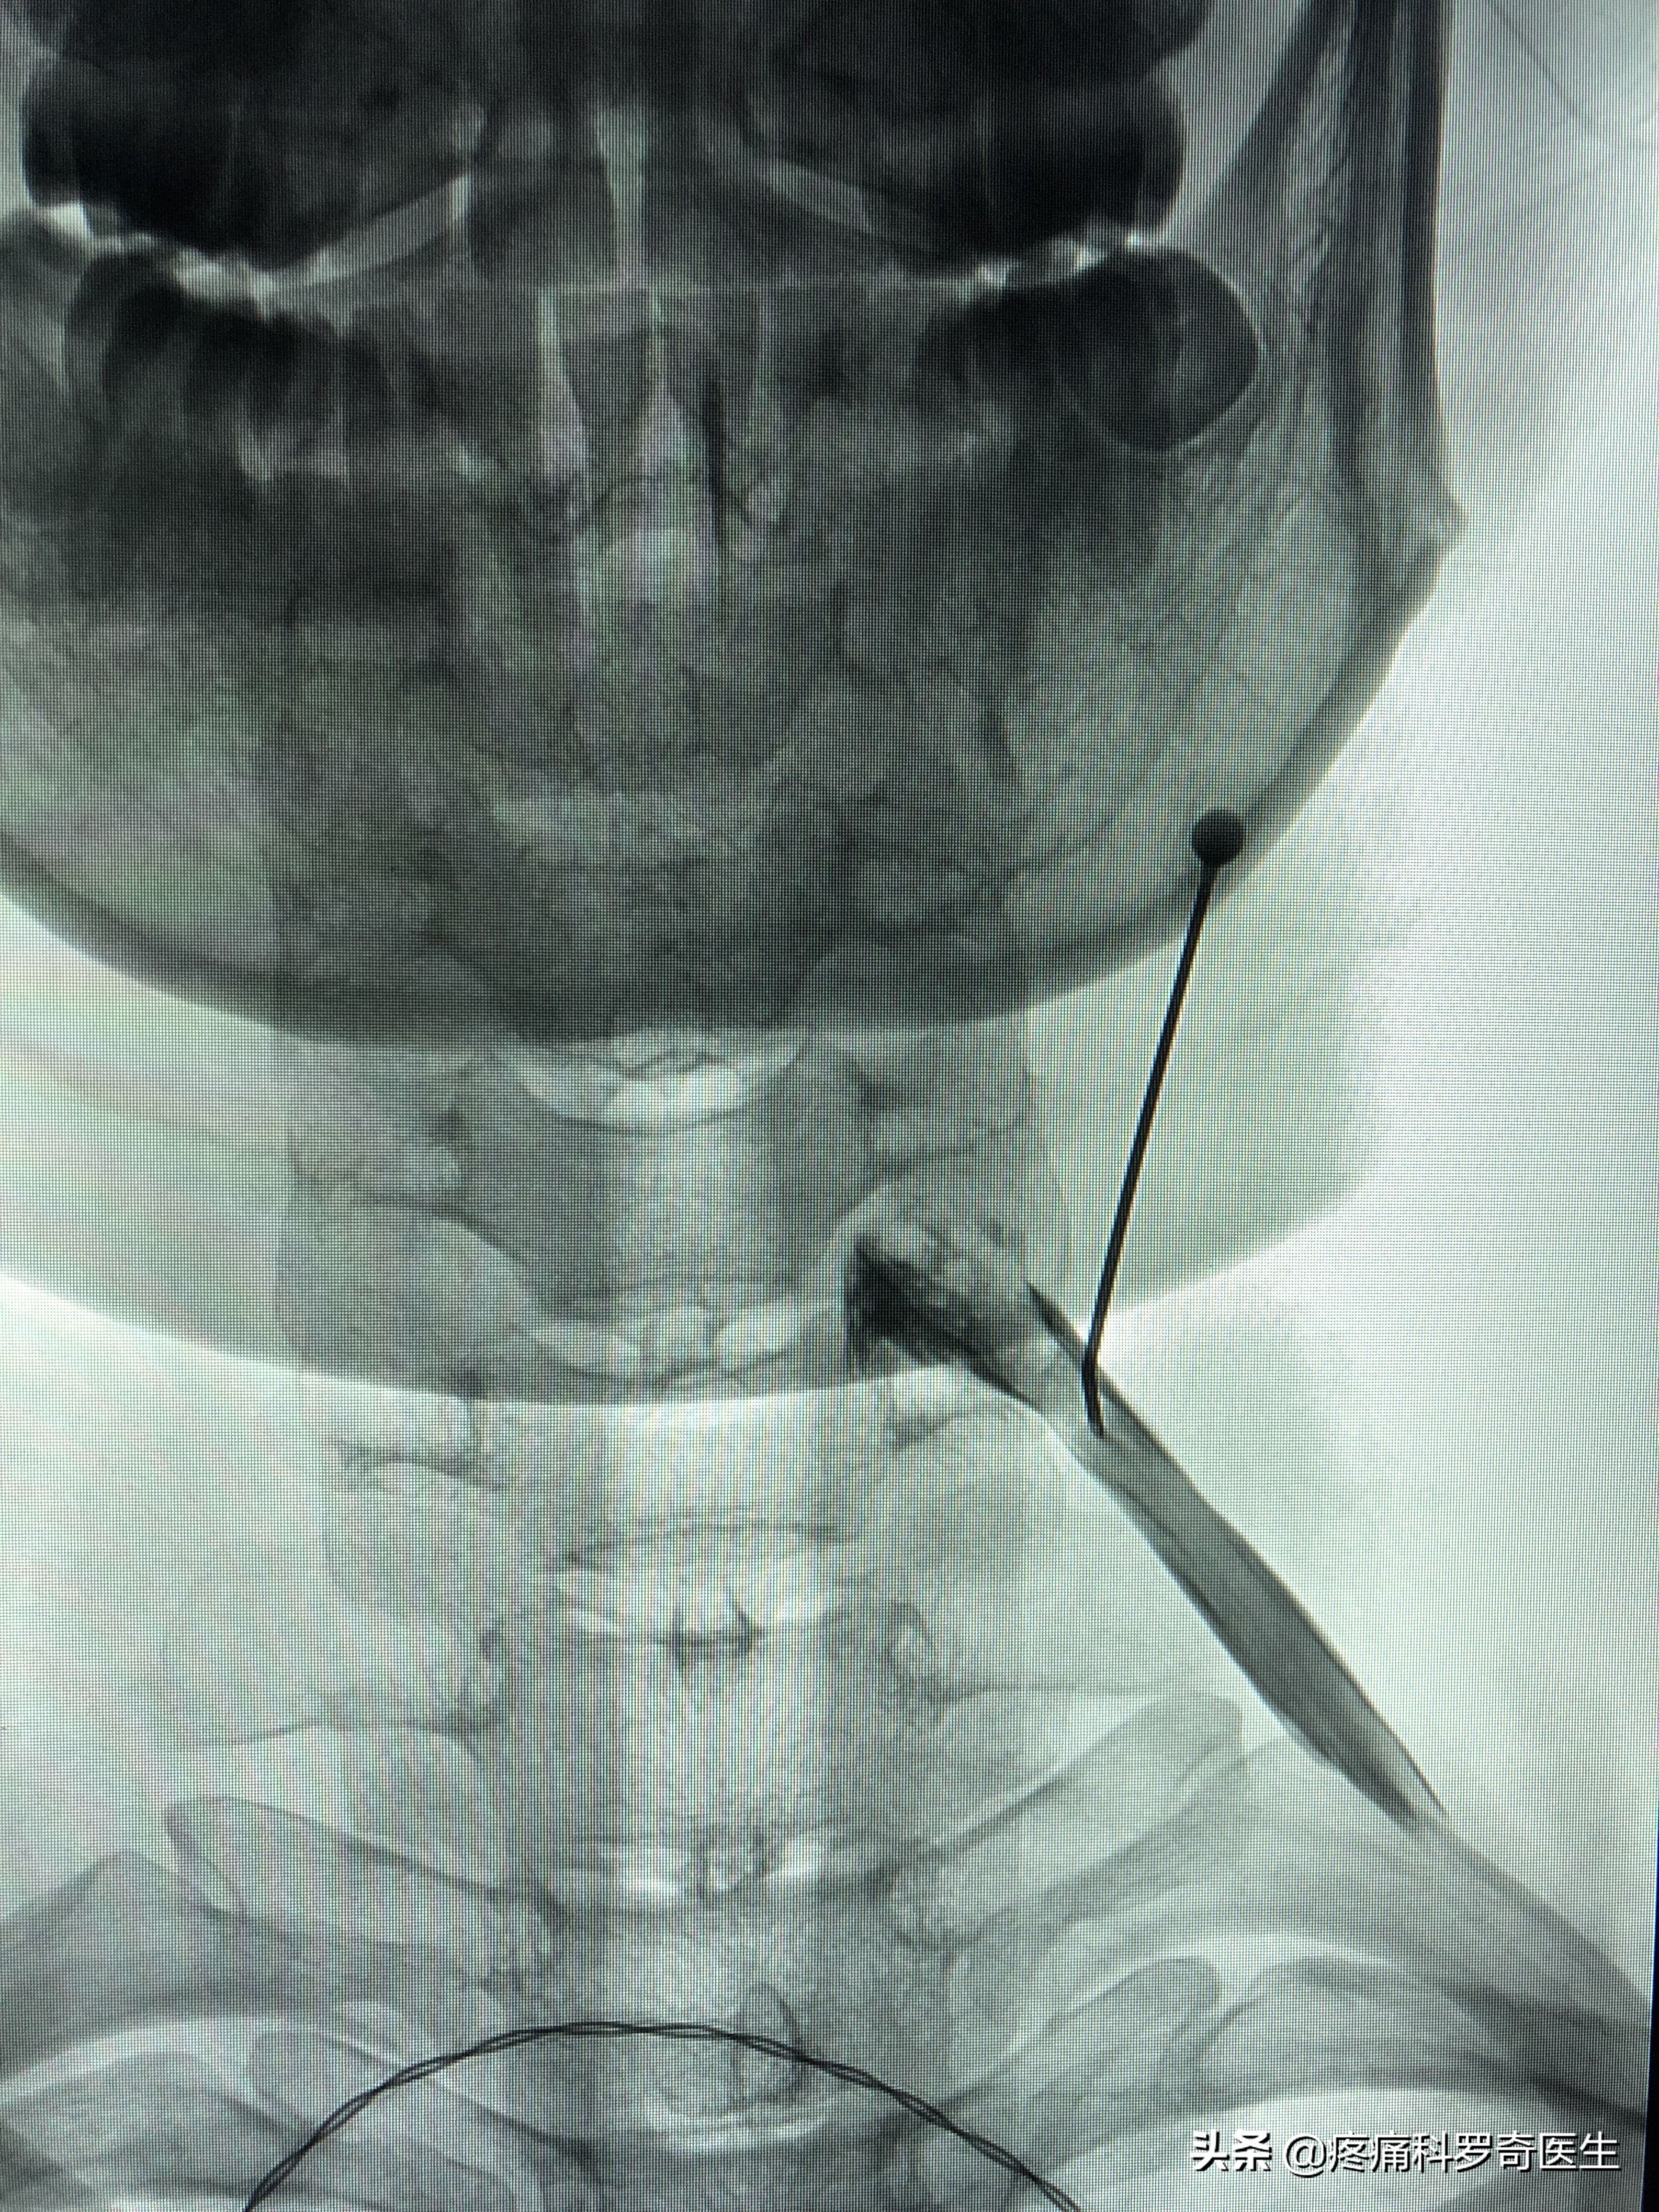

颈椎内热针软组织松解治疗

图片中,就是我们平时做的内热针治疗,它是一种比小针刀效果更强的软组织治疗手段(以前我们都做小针刀,后来有了这个技术,小针刀基本就被淘汰了),内热针治疗做得好的话,一次治疗顶你做十多天的理疗。